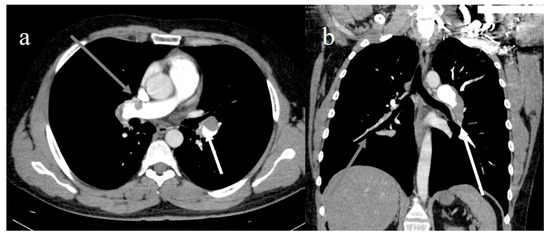

- Léonard-Lorant, I.; Delabranche, X.; Séverac, F.; Helms, J.; Pauzet, C.; Collange, O.; Schneider, F.; Labani, A.; Bilbault, P.; Molière, S.; et al. Acute Pulmonary Embolism in Patients with COVID-19 at CT Angiography and Relationship to d-Dimer Levels. Radiology 2020, 296, E189–E191. [Google Scholar] [CrossRef] [Green Version]

- Lang, M.; Som, A.; Carey, D.; Reid, N.; Mendoza, D.P.; Flores, E.J.; Li, M.D.; Shepard, J.-A.O.; Little, B.P. Pulmonary Vascular Manifestations of COVID-19 Pneumonia. Radiol. Cardiothorac. Imaging 2020, 2, e200277. [Google Scholar] [CrossRef]

- Ooi, M.; Rajai, A.; Patel, R.; Gerova, N.; Godhamgaonkar, V.; Liong, S. Pulmonary thromboembolic disease in COVID-19 patients on CT pulmonary angiography—Prevalence, pattern of disease and relationship to D-dimer. Eur. J. Radiol. 2020, 132, 109336. [Google Scholar] [CrossRef]

- Spagnolo, P.; Cozzi, A.; Foà, R.A.; Spinazzola, A.; Monfardini, L.; Bnà, C.; Alì, M.; Schiaffino, S.; Sardanelli, F. CT-derived pulmonary vascular metrics and clinical outcome in COVID-19 patients. Quant. Imaging Med. Surg. 2020, 10, 1325–1333. [Google Scholar] [CrossRef]